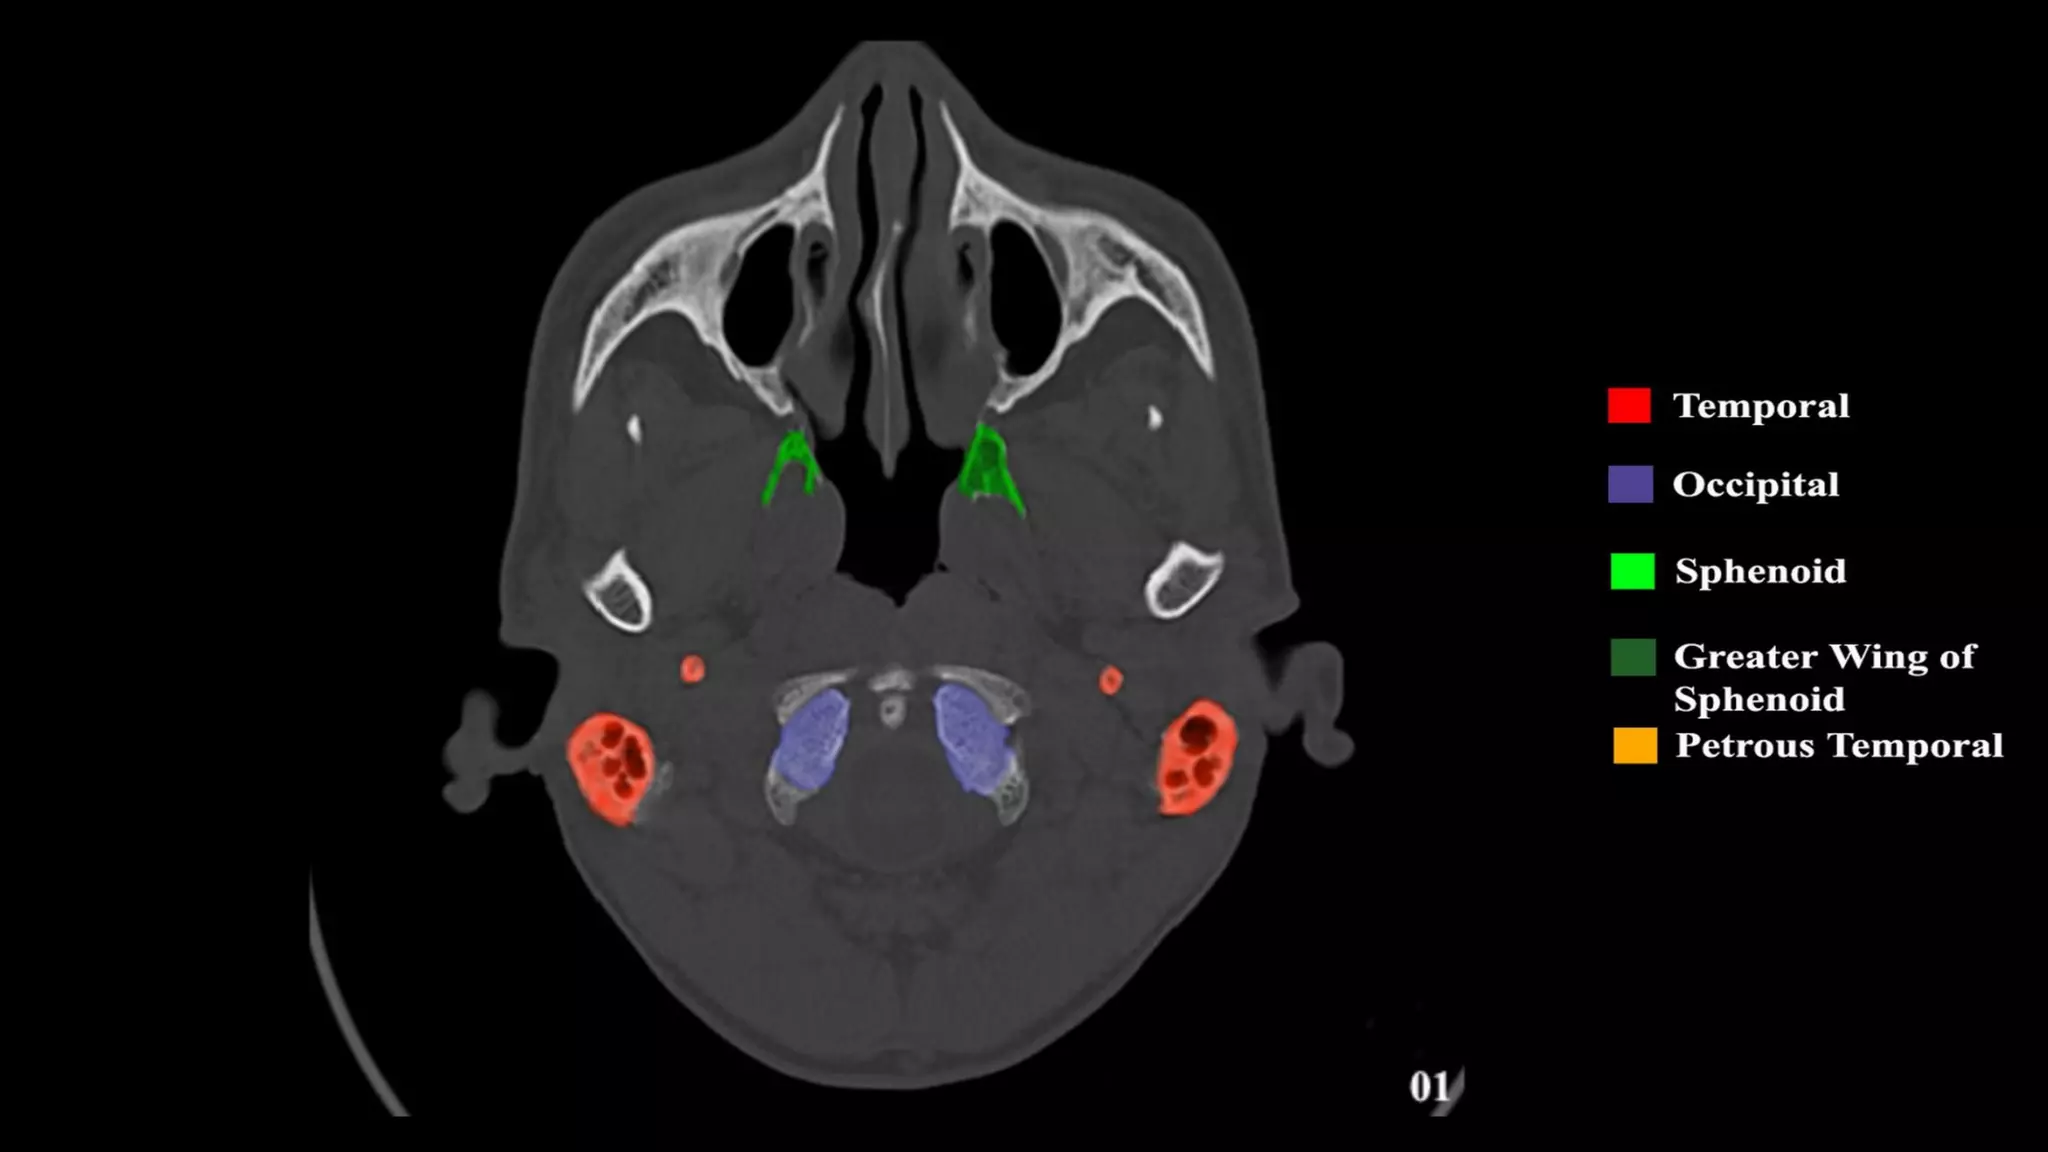

Pseudo-fractures

Extrinsic Fissures &

Sutures